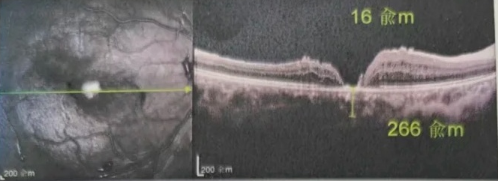

去年年底,年逾7旬的吳爺爺突然發(fā)現(xiàn)右眼看不清,且看東西變形,到當(dāng)?shù)蒯t(yī)院檢查后確診黃斑裂孔。此后他輾轉(zhuǎn)求醫(yī),經(jīng)歷了兩次玻切聯(lián)合內(nèi)界膜剝除術(shù),每次術(shù)后都嚴(yán)格“趴睡”一個(gè)月。然而結(jié)果令人失望:裂孔不但沒(méi)閉合,反而持續(xù)擴(kuò)大,甚至還并發(fā)高眼壓。

由于自身患有頸椎病,每次術(shù)后長(zhǎng)期的趴睡都讓他痛苦不堪。為了尋求更好的治療,吳爺爺來(lái)到廈門大學(xué)附屬?gòu)B門眼科中心,找到了眼外傷及眼底病2科的李海波博士后。此時(shí),吳爺爺右眼的黃斑裂孔已經(jīng)持續(xù)擴(kuò)大到780μm,演變?yōu)殡y治性的大裂孔。

最讓吳爺爺難以置信的是:術(shù)后只需保持平躺24小時(shí)!第二天復(fù)查時(shí),眼底鏡及OCT檢查清晰顯示——那個(gè)折磨了他大半年的大裂孔,竟然閉合了!且吳爺爺?shù)挠已垡暳τ辛嗣黠@的改善,術(shù)后3天已經(jīng)可以看到 0.15。